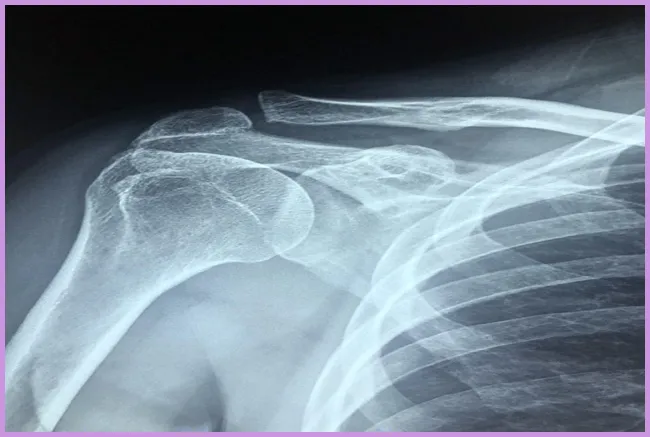

어깨 석회질의 진단

어깨 석회질을 진단하기 위해서는 의사의 진료와 함께 X선 검사를 통해 석회 침착 여부를 확인해야 합니다. 통증이 계속되거나 일상생활에 지장을 주는 경우, 반드시 전문의를 찾아 정확한 검사를 받는 것이 중요합니다.